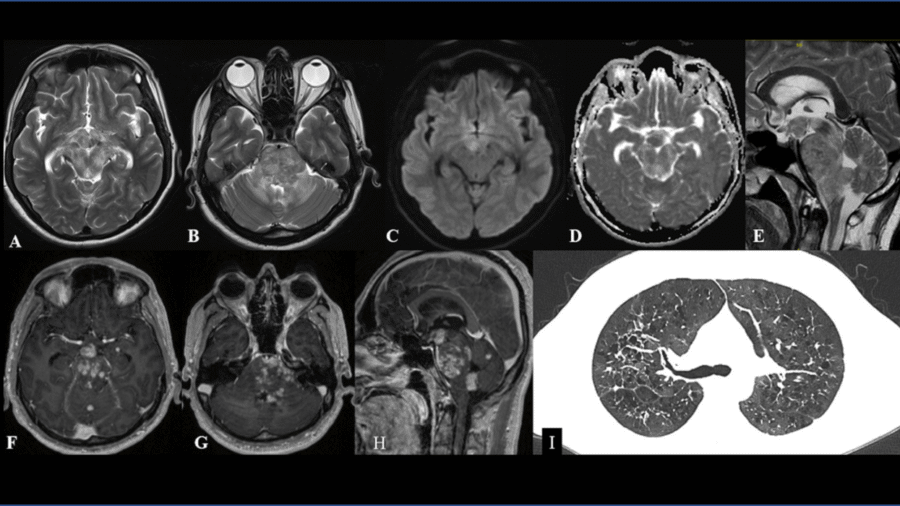

11 year old female child presented with history of right sided hearing loss, vertigo and imbalance since 6 months, right facial numbness, facial asymmetry and difficulty swallowing since 3 months, headache and vomiting since 1 month duration.